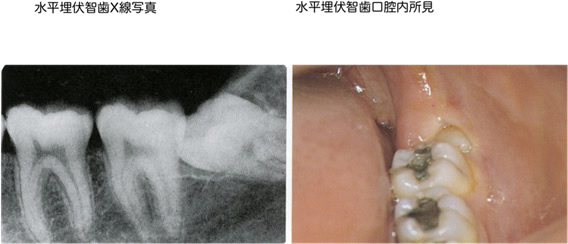

親不知(おやしらず)の抜歯

通常成人の歯は28本あります。上下顎それぞれ、左右に7本づつ生えています。8番目の歯は18歳以降に生えてくるため、親が知らない時に生えてくることから一般的に親知らずと呼ばれています。学術的には第3大臼歯、智歯といい、咬み合わせに関与していないことが多い歯です。

一番奥に生えている親知らずは清掃しにくく不潔になりやすく虫歯にもなり易いとされています。また、親知らずの前に位置する歯(第2大臼歯)の清掃不良を引き起こし同歯が虫歯になる原因になります。また、ばい菌が感染症を引き起こし、顎の腫れ、痛み、発熱、発赤、開口障害などを引き起こします。ひどくなると摂食障害、気道閉塞を引き起こすこともあります。

抜歯後にも痛みや腫れを伴いますので、一度症状の出た親知らずは抜歯することをお勧めします。一時的に急性症状が治まっても、体調が悪くなった時に再度急性症状が出る可能性が高く、再燃時にはさらに悪化する可能性が高いからです。ただし、親知らずの根の先と、神経の管が近い場所を走っている場合には抜歯することによって神経を損傷することによって感覚の麻痺を生じることがあります。このため抜歯する、または残存させておく、それぞれのリスクについて説明させていただく場合もあります。